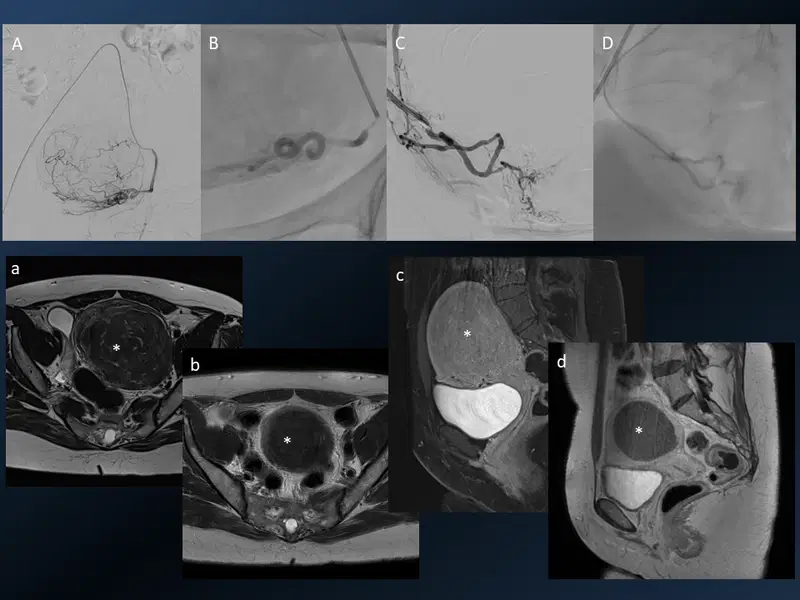

14. Uterine fibroid embolization (UFE)

Uterine fibroid embolization (UFE)

Young lady with severe menorrhagia and anaemia. Superselective cannulation of the left uterine artery (A) which gives the predominant fibroid supply. Stasis in the artery after PVA particle embolization (B). Similar pre and post angiograms of the right uterine artery (C & D). MRI of the pelvis before (a & b) and 6 months after (c & d) UFE depicting excellent treatment response with shrinkage and absent enhancement of the fibroid (*). There was complete relief from menorrhagia.